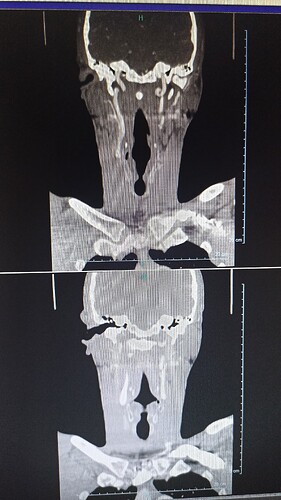

This was a scan with contrast I had the injection I have hundreds of images on the disk but I can’t see the viens so I’m very confused

Hopefully these images can give a better view

The veins are visible in your second set of images but not the first. Sorry I didn’t see the vascular images when I wrote my post.

The left IJV does not looked compressed & neither does the right but the IJV isn’t totally visible on the right so I don’t know for sure. Because of the angles of your styloids, it’s possible you have internal carotid artery (ICA) compression but I can’t see evidence of that either.

It really seems the styloid thickness & steep angle of styloid growth are most likely what the problem is. Please don’t take what I’ve said as diagnostic. It’s just my opinion.

Hopefully others with more knowledge will comment, I can’t see any obvious compression, but sometimes just the styloid touching an artery can be enough to irritate it & cause symptoms, I may be wrong but the hyoid on the left side looks quite close to the carotid bifurcation, where the carotid artery divides into internal & external arteries, this is just a guess though…

Good call, @Jules! Actually, I think the hyoid looks close to the carotid bifurcation on both sides & may even be poking it on the right side.

The left side is very similar so I didn’t annotate it.